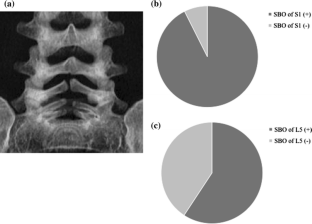

Among the 30 patients, 27 (21 boys, 6 girls) had L5 spondylolysis (90.0 %). Only 2 patients had no history of athletic activity at the first consultation. All patients, except for 2 whose diagnosis was incidental, complained of low back pain. In the 27 patients with L5 spondylolysis, 17 (63.0 %) had terminal-stage fracture and 25 (92.6 %) had spina bifida occulta (SBO) involving the S1 lamina. Sixteen of the 27 (59.3 %) had SBO involving the affected lamina (L5) and S1 lamina. In contrast, the 3 patients with L3 or L4 spondylolysis had no evidence of SBO. With respect to skeletal age, 23 of the 27 L5 spondylolysis patients (85.2 %) were in the cartilaginous stage while the remaining 4 patients were in the apophyseal stage.